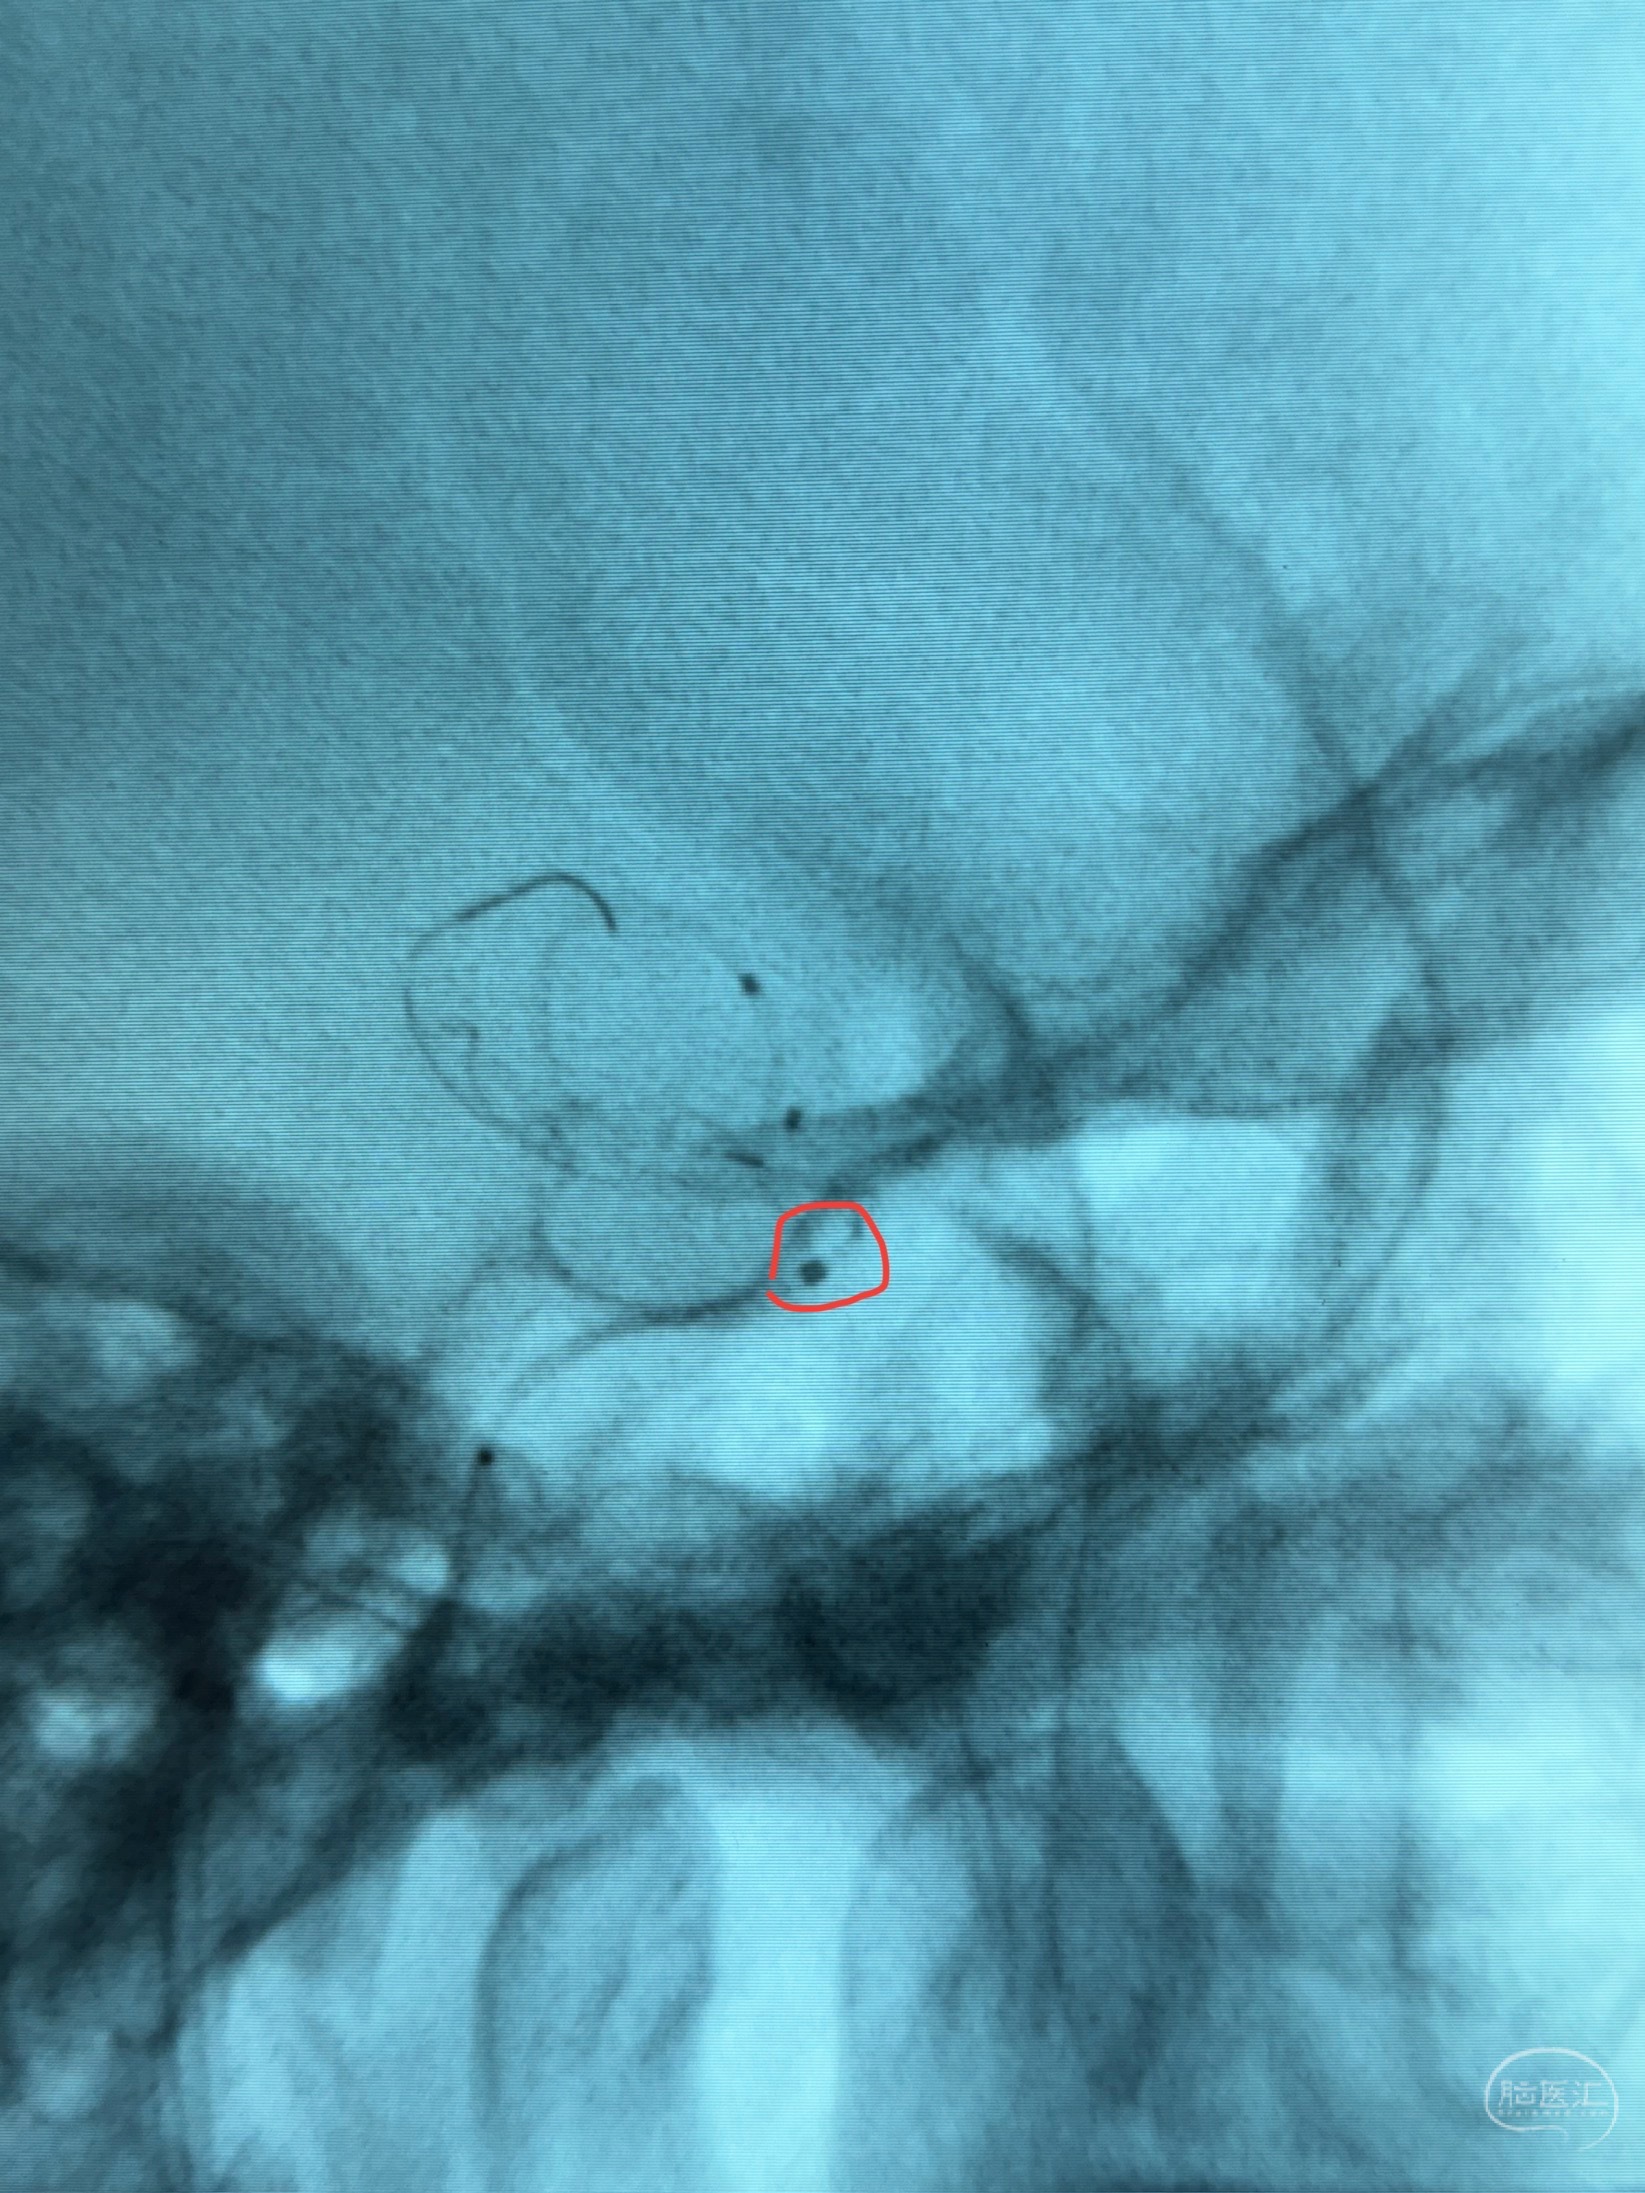

透视可见红圈部分为支架导管的头端

手推冒烟显示支架位置及展开情况,箭头为支架导管的位置

尝试回收支架失败,只能考虑释放支架了

逐帧图像展示歪着脖子释放支架,旁边吩咐助手手机摄影、拍照留像(透视机不能留影像)